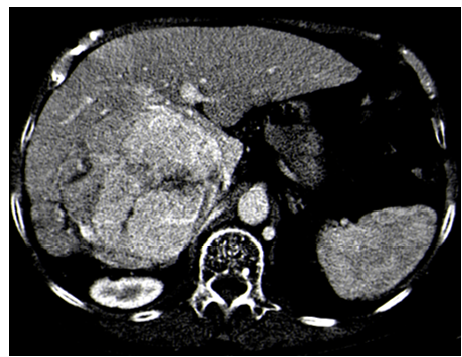

Solid Pseudopapillary Tumor of the Pancreas: A Case Report

Lamara Abdelhak, Medjahdi Sid Ahmed, Gadda Mounir, Boukhane Mohamed, Nahida Harchouche, Bloulou Mamed Lamine, Saadna Adlene and Selmani Khaled. 6(7): 12-18.